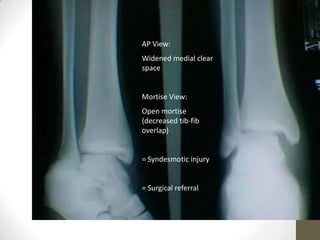

Syndesmotic disruption:

• On the AP radiograph syndesmotic disruption

is indicated by a

• Tibial Clear Space >5mm

• Tibio Fibular Overlap <10mm

• On the mortise view a

• Tibio Fibular Overlap <1mm

AP View:

Widened medial clear

space

Mortise View:

Open mortise

(decreased tib-fib

overlap)

= Syndesmotic injury

= Surgical referral